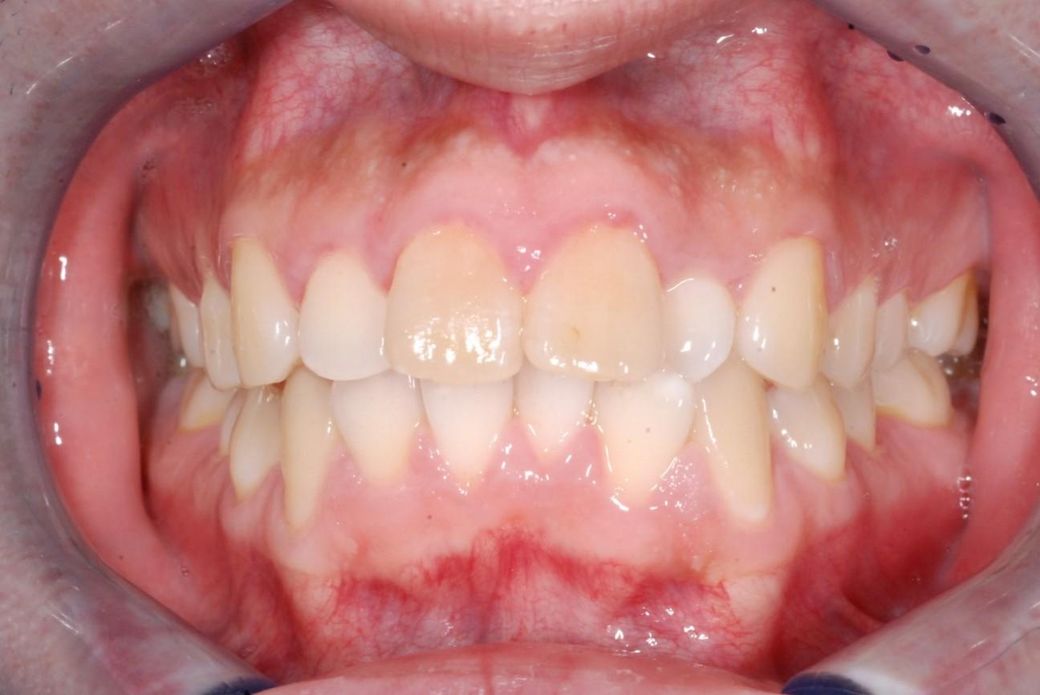

교정 마무리 단계가 되어 충치 치료중 위쪽 앞니 2개가 신경이 죽어 치아색이 누런걸 확인하였습니다.

정확히는 교정 전부터 신경이 죽어있었습니다.

관련 사진 첨부합니다.

• 1번 째 사진

• 2번 째 사진